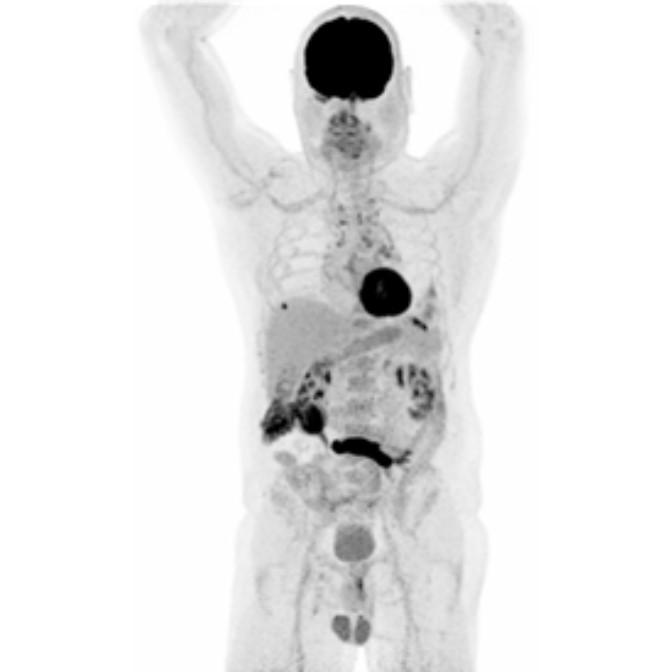

Partial nml and melanoma PET scan

The goal of PET/CT imaging in oncology is to enable the physician to distinguish between benign and malignant pathologies, to determine the extent of disease, to detect residual and recurrent tumors, to monitor the effectiveness of treatments, and to guide therapies.